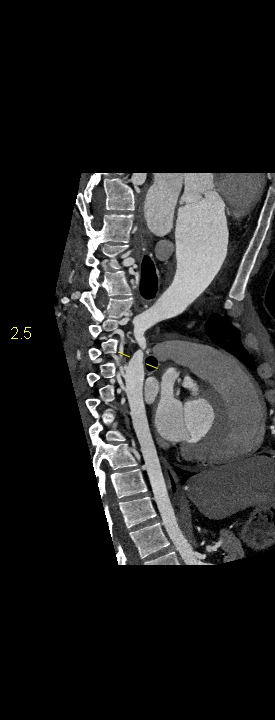

Figurile 1-5: reconstrucții multiplanare din achiziție angioCT aorta toracică

Discuţie caz nr 109: Pacient cu suspiciune de coarctaţie de aortă – are indicație de angioCT aortă toracică; medicul radiolog la acești pacienți este indicat să efectueze investigația cu sincronizare ECG deoarece coarctaţia de aortă poate fi asociată și cu bicuspidie de valvă aortică, mai ales că la acest pacient ecografia cardiacă descria creștere de calibru a aortei ascendențe. Pe reconstrucția cine în planul valvei aortice din achiziția cardioCT cu sincronizare ECG se remarcă o valvă aortică morfologic tricuspidă, funcțional bicuspidă ce asociază ectazie de aortă ascendentă și coarctaţie de aortă descendentă cvasicompletă cu dezvoltare de circulație colaterală intercostală și mamară internă.